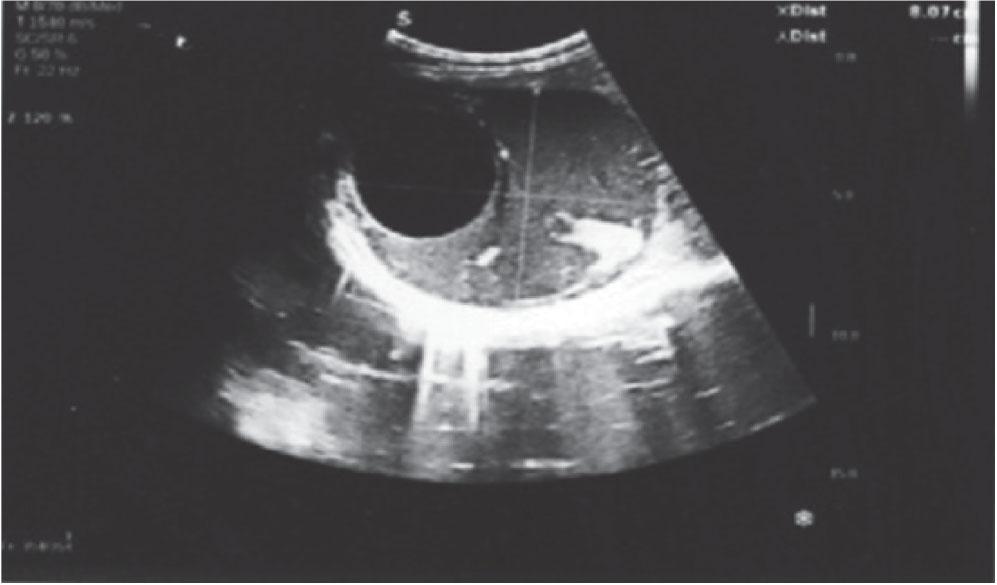

Abdominal ultrasound indicated the presence of multiple cystic formations in the left hemiabdomen and a cyst in in segment VIII of the liver (right lobe, subdiaphragmatic), measuring 10.5 × 8 cm (Figure 1). This prompted a comprehensive differential diagnosis to rule out other potential cystic lesions, such as liver abscess or simple, neoplastic, or congenital cysts.

Right hepatic lobule with hypoechoic avascular formation (cyst)

Left hemiabdomen entirety filled with multiple cystic septated formations